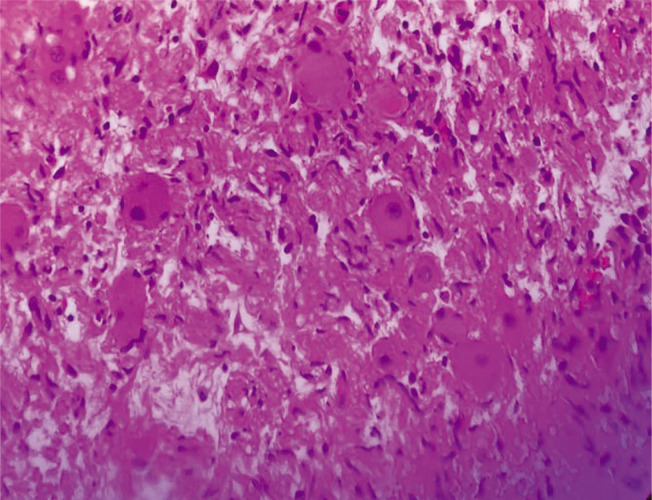

速发性肥胖伴下丘脑功能障碍、通气不足、自主神经失调和神经嵴肿瘤(ROHHAD-NET)虽然是一种罕见的疾病,但具有潜在的致命性。了解和紧急诊断是至关重要的。我们在此报道三起连续案件,这是印度首次发生此类案件。18个月以上的儿童通常以体重快速增长为主要症状。下丘脑功能障碍可能导致内分泌问题、呼吸功能障碍和自主神经失调。多年来,随着时间的变化,出现一种或多种下丘脑功能障碍的迹象:高泌乳素血症、生长激素缺乏症、中枢性甲状腺功能减退症、中枢性肾上腺功能不全或库欣综合征、青春期提前或延迟、水电解质平衡紊乱。诊断是困难的,因为没有可靠的测试,治疗主要是支持性的。这三个发育良好的孩子都表现出体重迅速增加,然后出现了下丘脑功能障碍的症状。其中一个偶然发现神经嵴肿瘤,第二个有持续性高钠血症,第三个孩子表现为肠梗阻。各种各样的表现和模糊的症状谱对临床医生的诊断提出了挑战,并强调了创造意识的重要性。由于临床上很难将ROHHAD综合征与其他遗传来源的肥胖综合征区分开来,因此需要个性化的策略方法。

Rapid-onset obesity with hypothalamic dysfunction, hypoventilation, autonomic dysregulation and neural crest tumor (ROHHAD-NET) though a rare disease, is potentially fatal. It is of utmost importance to be understood and urgently diagnosed. We hereby report a series of three cases, the first of its kind from India. Children older than 18 months old usually exhibit rapid weight growth as a presenting symptom. Hypothalamic dysfunction could lead to endocrine issues, respiratory dysfunction and autonomic dysregulation. Over the years, with variable timing, one or more signs of hypothalamic dysfunction appear: hyperprolactinemia, growth hormone deficiency, central hypothyroidism, central adrenal insufficiency or Cushing syndrome, early or delayed puberty, water-electrolyte balance disorders. The diagnosis is difficult because there is no reliable test, and the treatment is mainly supportive. All the three children who were thriving well, presented with rapid weight gain and then developed symptoms of hypothalamic dysfunction. While in one a neural crest tumor was incidentally detected, the second had persistent hypernatremia and the third child presented with intestinal obstruction. The varied presentation and vague symptom spectrum exhibit a diagnostic challenge to the clinician and underscores the importance of creating awareness. An individualized strategic approach is needed as it is clinically difficult to distinguish ROHHAD syndrome from other obesity syndromes of genetic origin.